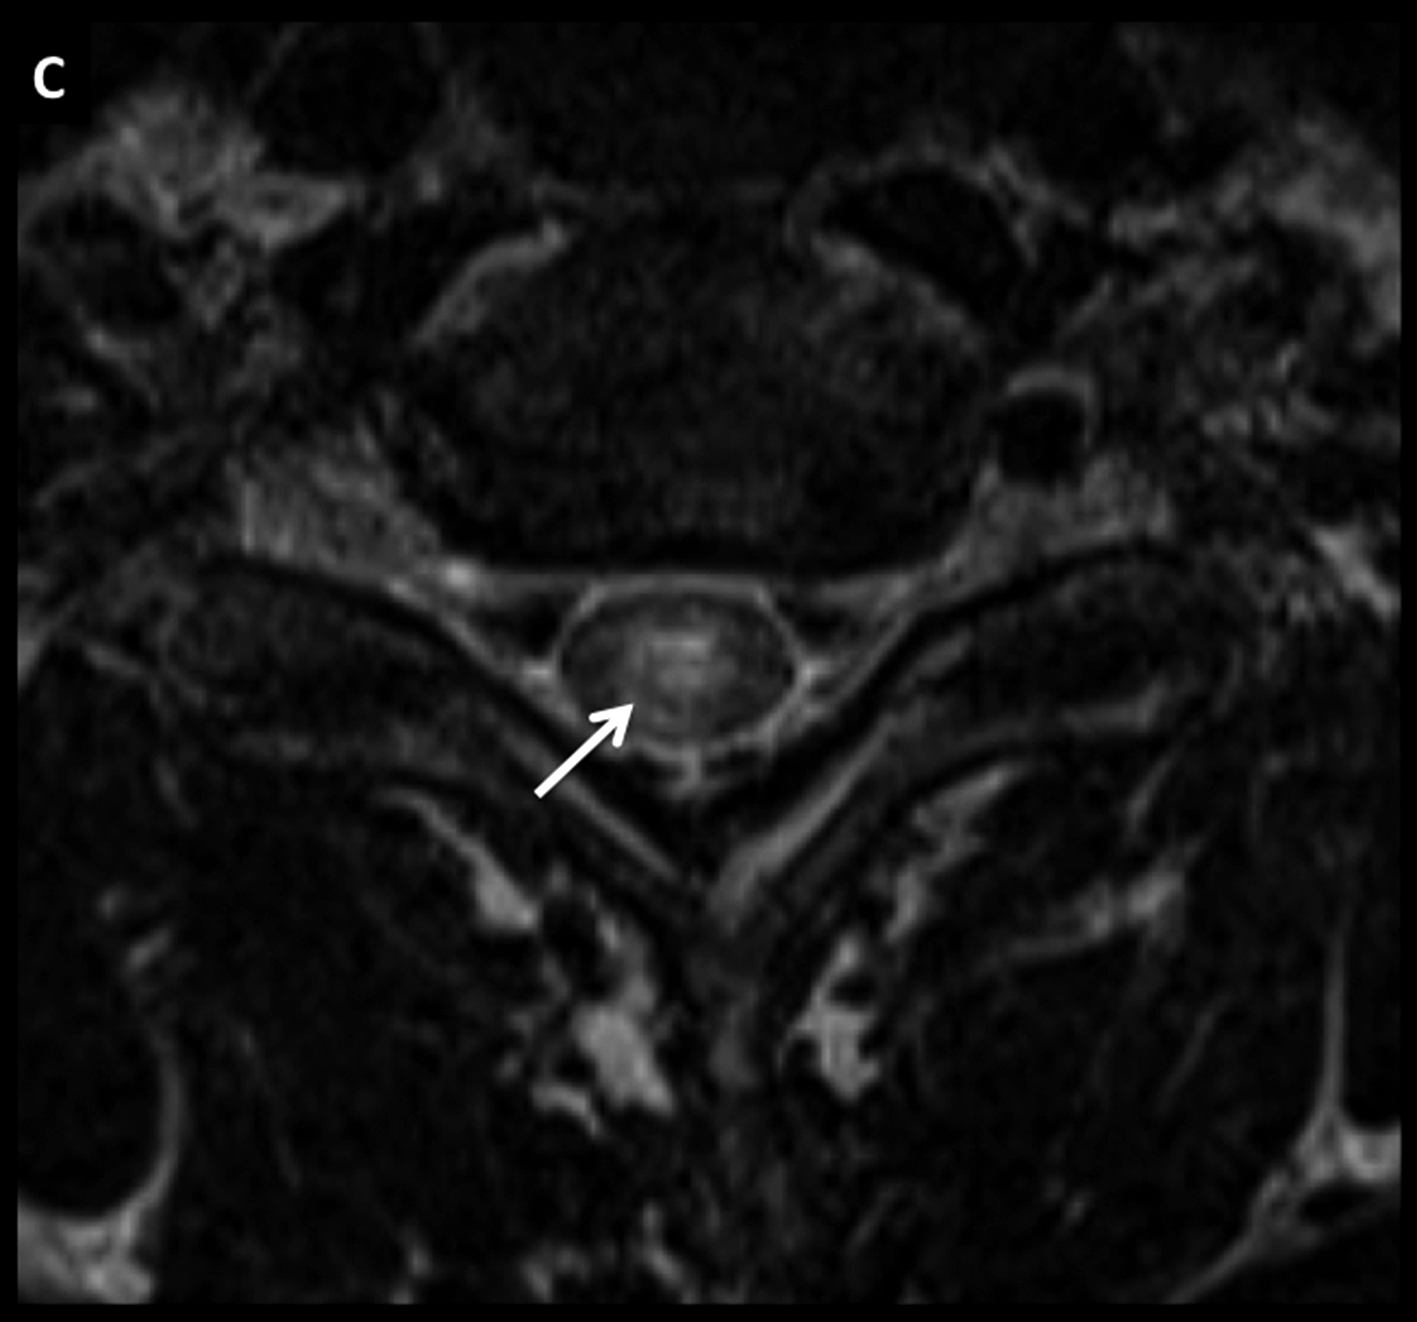

Figura 8

Paciente de 54 años con síndrome medular de instalación progresiva. En RM se identifica lesión medular cervical con ensanchamiento focal de varios segmentos, con alta intensidad de señal en secuencia T2 (A) y realce lineal, intenso, en secuencia T1 post-gadolinio (B).

En secuencia T2 en el plano axial (C) la alteración es heterogénea, centro-medular. Se decidió realizar biopsia de este proceso y el estudio histopatológico confirmó el diagnóstico de linfoma. Luego de la valoración sistémica no se evidenció compromiso asociado en otros territorios por lo que el diagnóstico final fue de LNH primario.